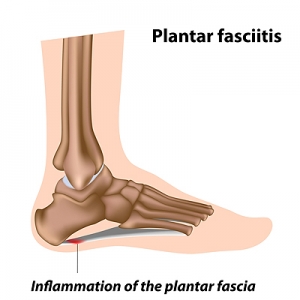

Plantar fasciitis is a common foot condition that many patients suffer from. It occurs when the plantar fascia becomes inflamed and can cause severe difficulty in walking. The plantar fascia is a band of tissue that connects the heel to the toes, and is found along the sole of the foot. Plantar fasciitis can be caused for a variety of reasons, including standing on hard surfaces for the majority of the day, wearing shoes that do not fit correctly, or it may come from having low or high arches. The pain is often felt in the heel and may be worse upon arising in the morning. It can help to perform specific stretches, and mild relief may be found when supportive insoles are worn. In severe cases, splints may have to be worn while sleeping, and this may help to stretch the feet. If you have heel pain, it is strongly suggested that you seek the counsel of a podiatrist who can effectively treat plantar fasciitis.

Plantar fasciitis is a common foot condition that many patients suffer from. It occurs when the plantar fascia becomes inflamed and can cause severe difficulty in walking. The plantar fascia is a band of tissue that connects the heel to the toes, and is found along the sole of the foot. Plantar fasciitis can be caused for a variety of reasons, including standing on hard surfaces for the majority of the day, wearing shoes that do not fit correctly, or it may come from having low or high arches. The pain is often felt in the heel and may be worse upon arising in the morning. It can help to perform specific stretches, and mild relief may be found when supportive insoles are worn. In severe cases, splints may have to be worn while sleeping, and this may help to stretch the feet. If you have heel pain, it is strongly suggested that you seek the counsel of a podiatrist who can effectively treat plantar fasciitis.

Plantar fasciitis is the inflammation of the thick band of tissue that runs along the bottom of your foot, known as the plantar fascia, and causes mild to severe heel pain.

Plantar fasciitis is one of the most common causes of heel pain. The plantar fascia is the thick band of tissue that connects the heel bone to the toes. When this band of connective tissue becomes inflamed, plantar fasciitis occurs. Fortunately, this condition is treatable.

There are several factors that may put you at a greater risk for developing plantar fasciitis. One of the biggest factors is age; plantar fasciitis is common in those between the ages of 40 to 60. People who have jobs that require them to be on their feet are also likely to develop plantar fasciitis. This includes factory workers, teachers, and others who spend a large portion of their day walking around on hard surfaces. Another risk factor is obesity because excess weight can result in extra stress being placed on the plantar fascia.

People with plantar fasciitis often experience a stabbing pain in the heel area. This pain is usually at its worst in the morning, but can also be triggered by periods of standing or sitting. Plantar fasciitis may make it hard to run and walk. It may also make the foot feel stiff and sensitive, which consequently makes walking barefoot difficult.

Treatment for plantar fasciitis depends on the severity of the specific case of the condition. Ice massage applications may be used to reduce pain and inflammation. Physical therapy is often used to treat plantar fasciitis, and this may include stretching exercises. Another treatment option is anti-inflammatory medication, such as ibuprofen.

If you suspect that you have plantar fasciitis, meet with your podiatrist immediately. If left untreated, symptoms may lead to tearing and overstretching of the plantar fascia. The solution is early detection and treatment. Be sure to speak with your podiatrist if you are experiencing heel pain.